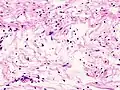

Illustrations

_S-100_immunostain.jpg)